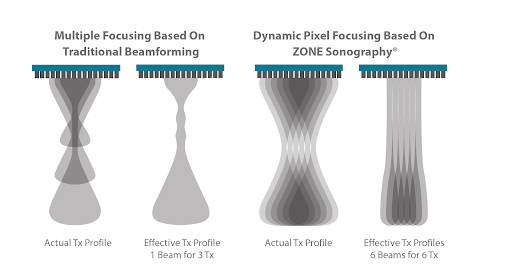

Динамическая фокусировка пикселей

Технология динамической фокусировки пикселей системы Resona 7 позволяет достичь непревзойденной однородности изображения всей области сканирования на уровне пикселей. Теперь нет необходимости настраивать фокусное расстояние для получения однородного изображения при проведении обследования пациента.